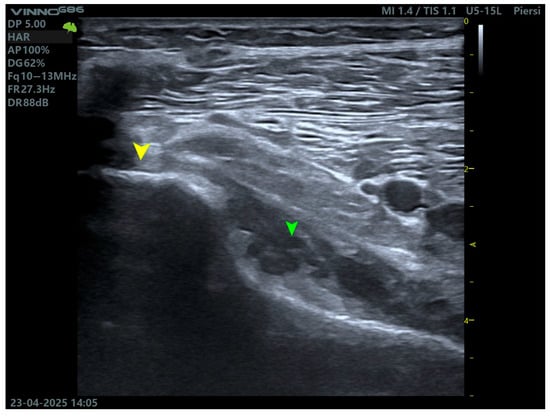

MRI is the gold standard for evaluating soft tissue structures in the knee, including the PT. Optimal visualization of the tendon is achieved using T1 and T2 weighted sequences (Figure 1 and Figure 2) with fat saturation in axial, coronal, and sagittal planes. The PT appears as a low signal intensity structure running obliquely from the lateral femoral condyle to the posteromedial tibia [1,15].

T2 sequence showing the tendon and multiplanar reconstruction. Yellow arrows indicate the tendon of the PM. Green arrows indicate the muscle belly of the PT.